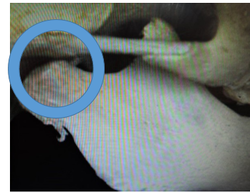

この写真の顎関節は小学校5,6年の形です。

顎関節の前方部の隆起が毎月、毎月成長していきます。

この為に、下顎骨を前方に適応させることが難しくなり上顎前突(出っ歯)の症状が突然目立ってきます。

この為に下顎骨を前方に適応させることが難しくなり、上顎前突(出っ歯)の症状が突然目立ってきます。